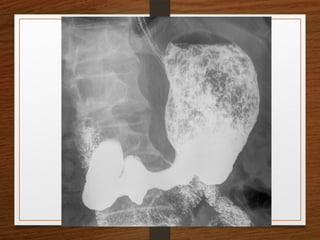

Doubt about the

diagnosis on the plain

radiographs

Contrast enema

• Features seen at the point of torsion include a

smooth, curved tapering of the colonic lumen, like a

hooked beak (the bird of prey sign)

• the mucosal folds often show a ‘screw’ pattern at the

point of twist